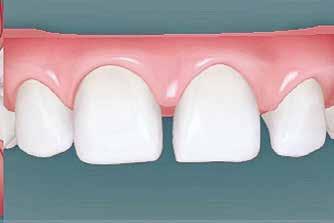

A szemfog oldalsó kismetsző helyére történő bemozgatása során a fog átalakítása javasolt a két fog eltérő morfológiai adottságai miatt (1. a-b. ábra). A fog kontúrozása, vagy úgynevezett formázása magába foglalja az approximális felszínek elcsiszolását, valamint a többi fogfelszín igazítását a kívánt fogformának megfelelően [1].

A kismetsző és szemfog klinikai koronái közötti eltérések a következőek: mezio-disztálisan keskenyebb oldalsó metsző, csücsök hiánya, egyenes éli lefutás, és a vesztibuláris felszín domborulata is kevésbé kifejezett [2,3]. A szemfoggal összehasonlítva, az oldalsó metsző rendszerint rövidebb és keskenyebb mind mezio-disztálisan, mind vesztibulo-orálisan. Az átformázott szemfog és az oldalsó metsző anatómiai alakja közötti egyezés függ az elülső zóna mint egység formájától is. Kataoke és Nishimura három alapformát határozott meg az elülső fogak tekintetében: négyszögletes, óvóid és háromszög formájú [4]. A frontfogak vesztibuláris felszínét a három kúp egységeként írják le (kúpos fejlődési mamelonok): meziális, disztális és centrális. A szemfogak esetén a három közül a központi a legdominánsabb, de nem ugyanez a helyzet az oldalsó metsző esetében. Háromszög alakú fogkorona esetén a meziális és disztális érvényesül jobban, négyszögletes formánál mindhárom egyenlő arányban domborodik, míg óvóid forma esetén a középső kerül túlsúlyba. Ennek megfelelően a szemfog csücskét el kell csiszolni, és kompozit felépítéssel az elülső anatómiai formához illő oldalsó metsző alakzatot kialakítani a szélső élek megfelelő hangsúlyozásával [5]. Amennyiben az elülső fogak formája háromszögletes, akkor kifejezett meziális és disztális felépítésekre lesz szükség. Négyszögletes forma esetén a szemfog meglévő centrális kúposságát kiegyensúlyozva építik fel a fogat. Az elülső fogak ovoid alakzata esetén a meziális és disztális kúposságot alig vagy egyáltalán nem hangsúlyozzák